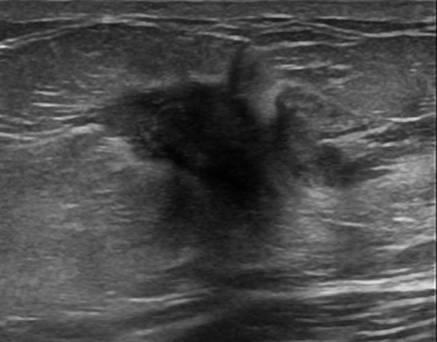

Ung thư vú

» Thông tin: Nữ giới – 55 tuổi.

» Lâm sàng: Khối tuyến vú.